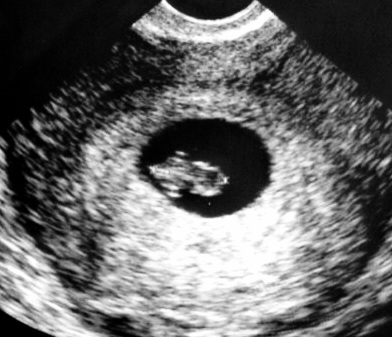

Tak mi už máme taky po kontrole. Jsem 7+0 a termín 19.5. Prcek má 8mm a Srdíčko bilo jako divé. Jinak mám teď všechno hrozně na rychlo. Za týden a den máme svatbu tak mám věcí až nad hlavu.